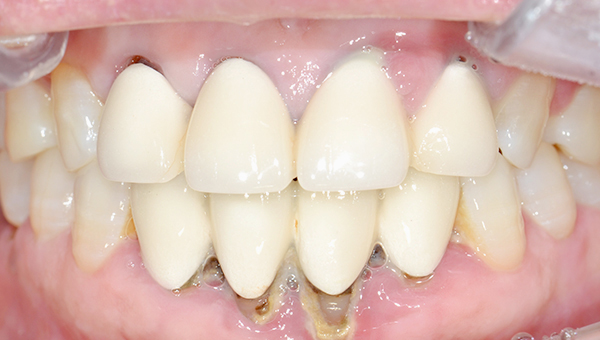

치료사례임플란트

강*란 임플란트 시술 사례

전체 임플란트

2025.02.07

치료 전

2025.08.19

치료 후